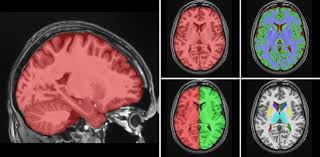

2D Cancer Annotation

Label Maps

R.I.P.

Ron Kikinis

B. Leonard Holman Professor of Radiology, Harvard Medical School

Download the same data to 3D Slicer using the IDC Browser extension!

Then, we will do Volume Rendering to analyze data and create a segmentation mesh of the tumor.

After export, let's load it in SliceDrop!